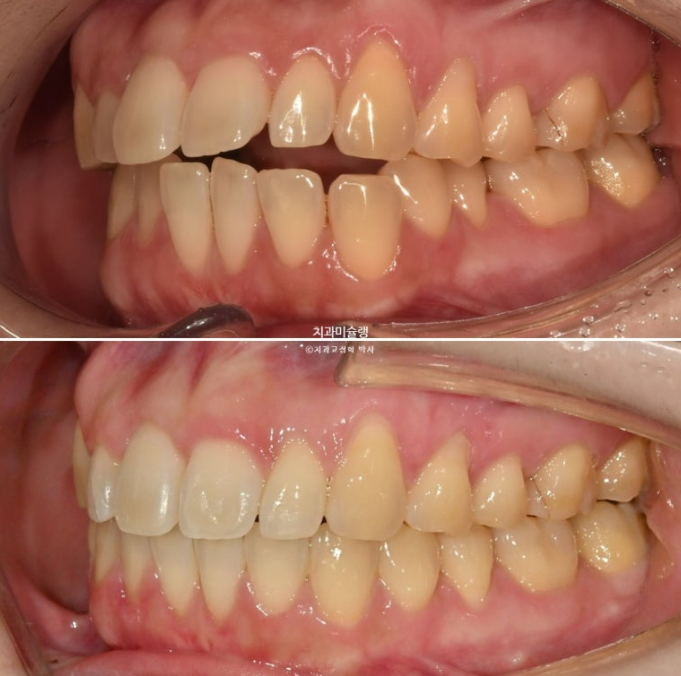

20년 전 교정을 했는데 재발이 되어 재교정을 위해 온 30대 환자분입니다.

아래 앞니 두 개 잇몸이 유독 내려가 있습니다.

정중선 기준 한쪽만 개방교합이 있는데 한쪽방향으로 혀내밀기 습관때문에 생긴 개방교합일 수 있고 유지장치 변형에 의해 치열이 일그러진 것 일수도 있습니다.

소구치에 윗니와 아랫니가 엇갈려 물리는 가위교합도 보입니다.

큰어금니 교합도 좋은 편 입니다.

24.06~25.11

아래 앞니 잇몸은 처음에 비해 소량 차올랐습니다. 앞니 뿌리가 치조골 안으로 안정적으로 들어가도록 치료계획을 세웠기 때문이고 이처럼 30대 성인이라도 가끔 회복되는 경우가 있습니다.